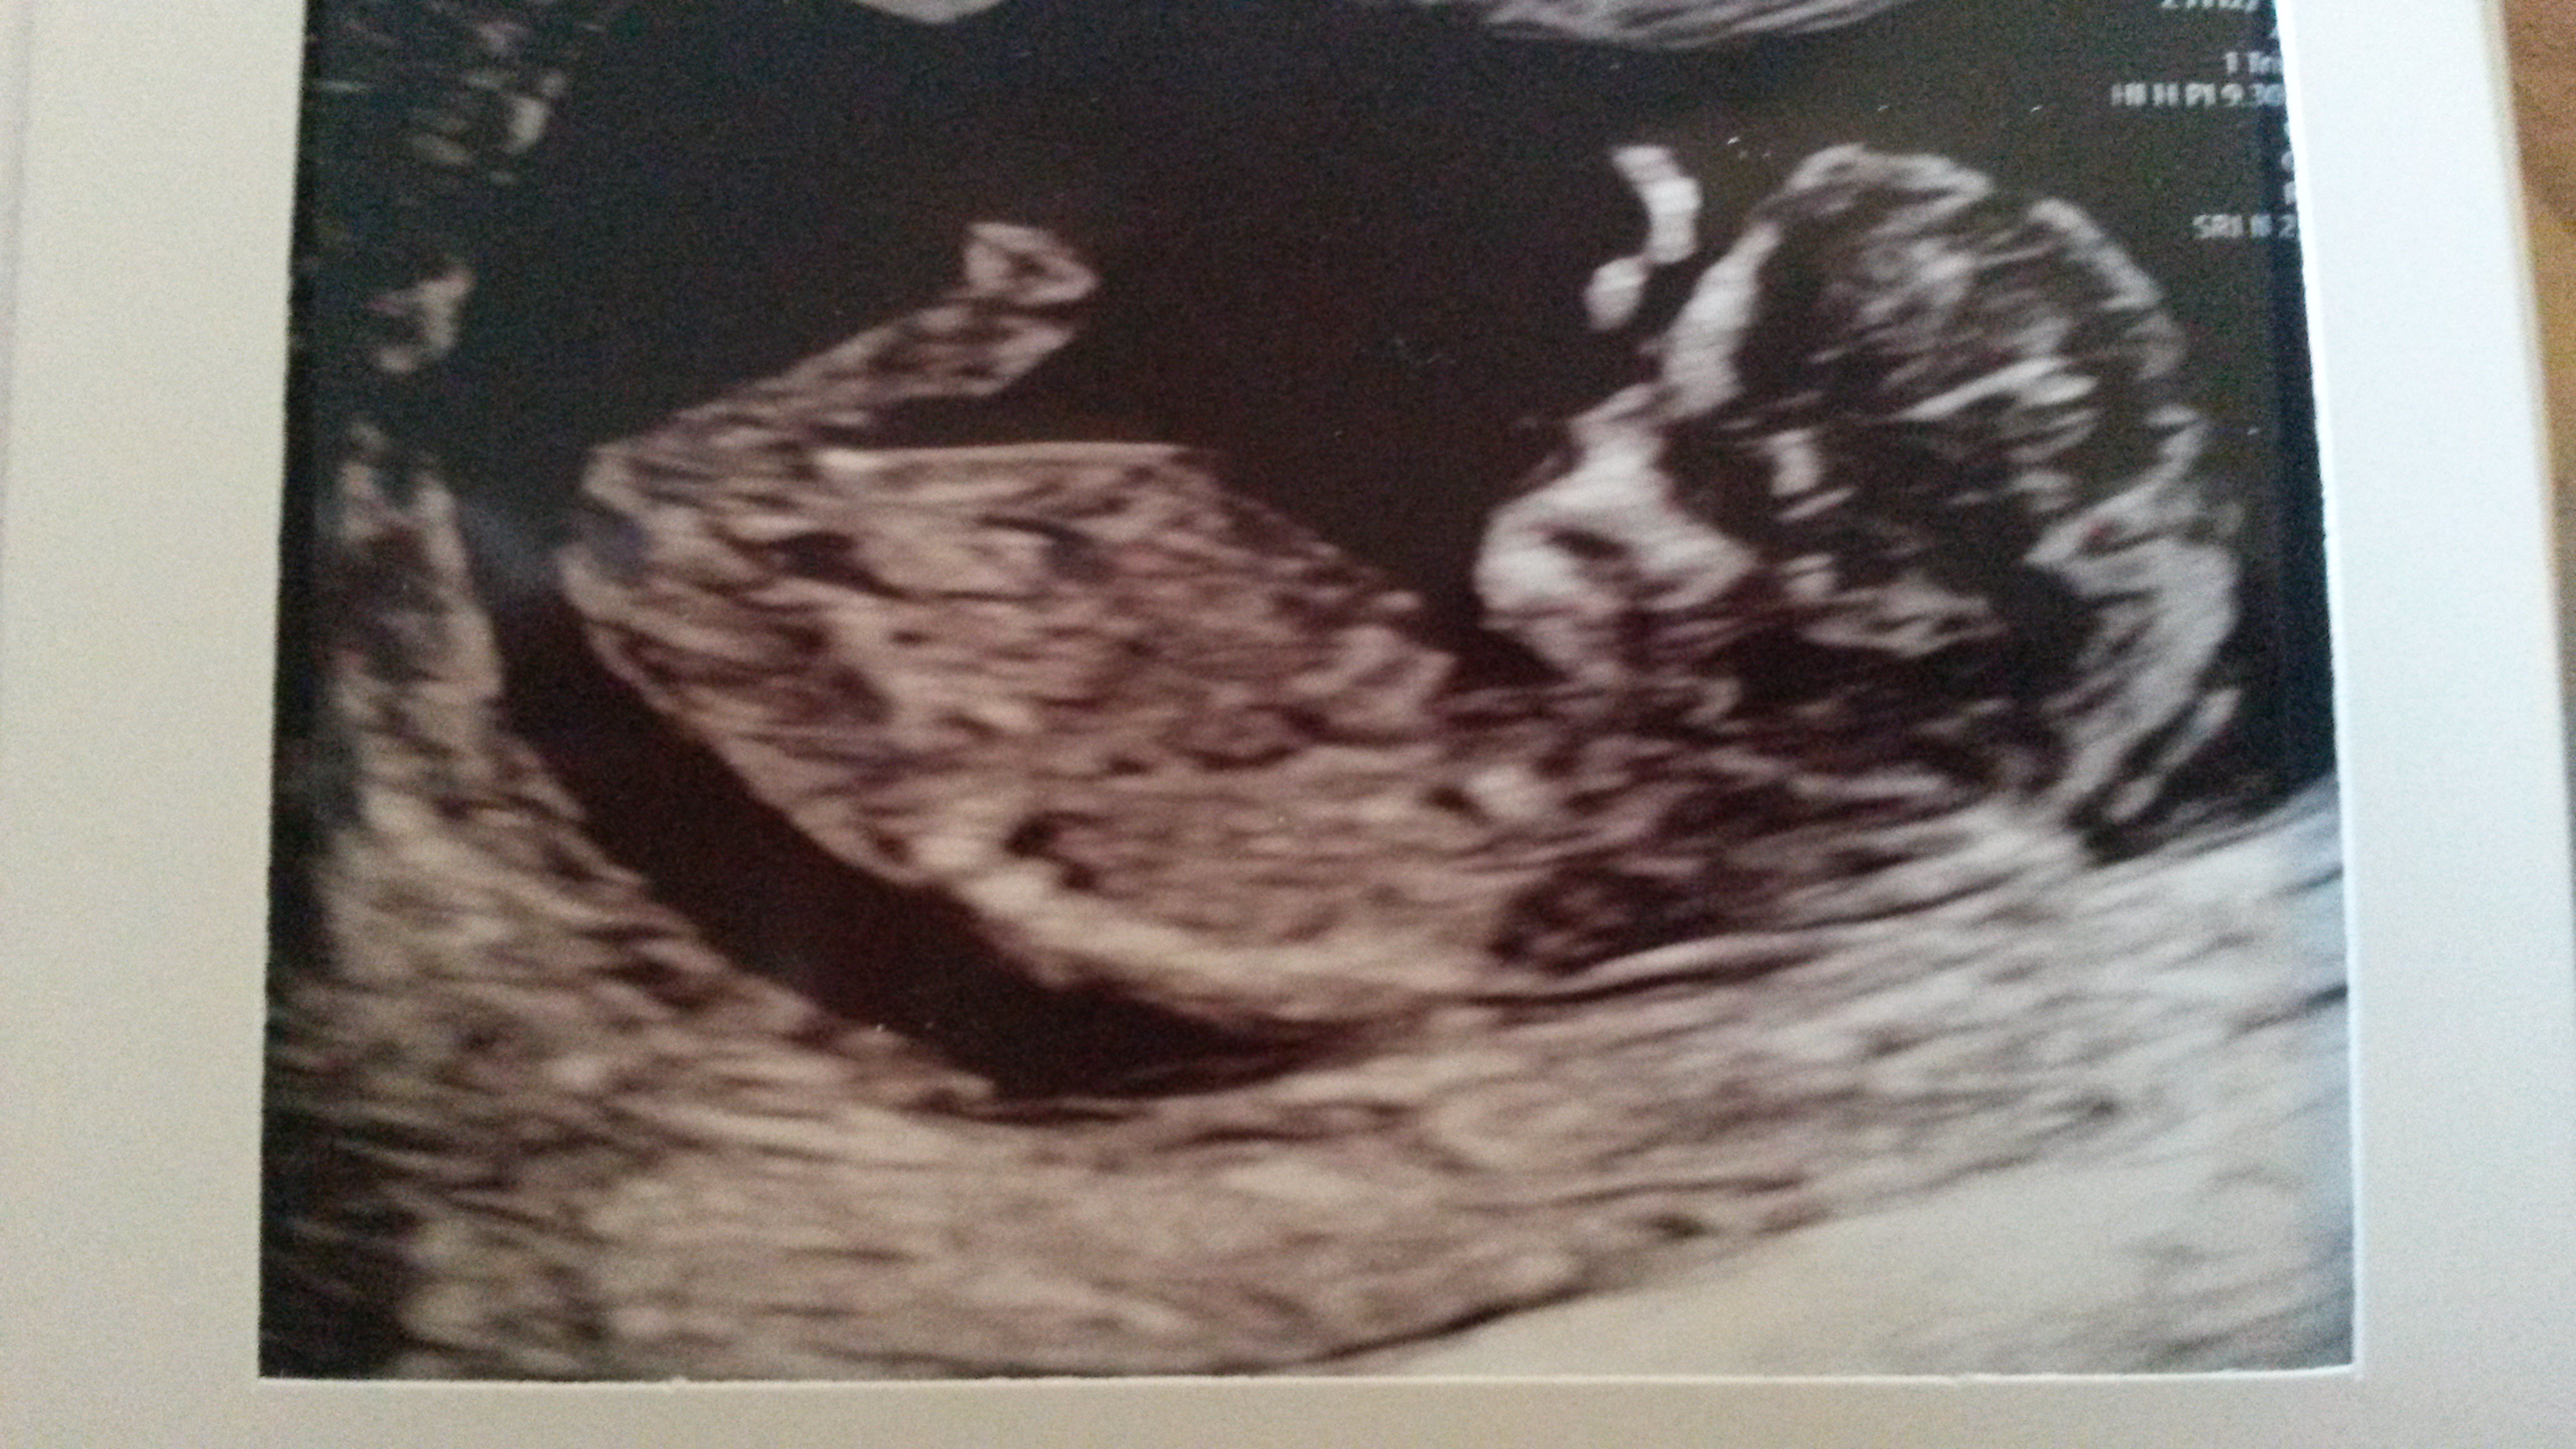

So no nub. Can I get anything off skull theory or is it still early?Attachment 41213dAttachment 41214